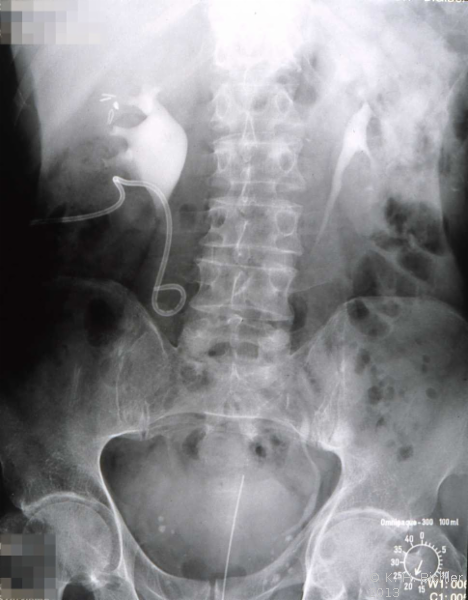

Als Komplikation ausgedehnter Mündungsdivertikel kommt es zu Abflussbehinderungen mit entsprechender Beeinträchtigung der Nierenfunktion. Als Beispiel die Harnstauungsniere bei einem Erwachsenen mit Abflussbehinderung durch ein ausgedehntes Mündungsdivertikel. Zunächst Harnableitung, dann Divertikelabtragung und Reimplantation (Abbildung HG1).

b